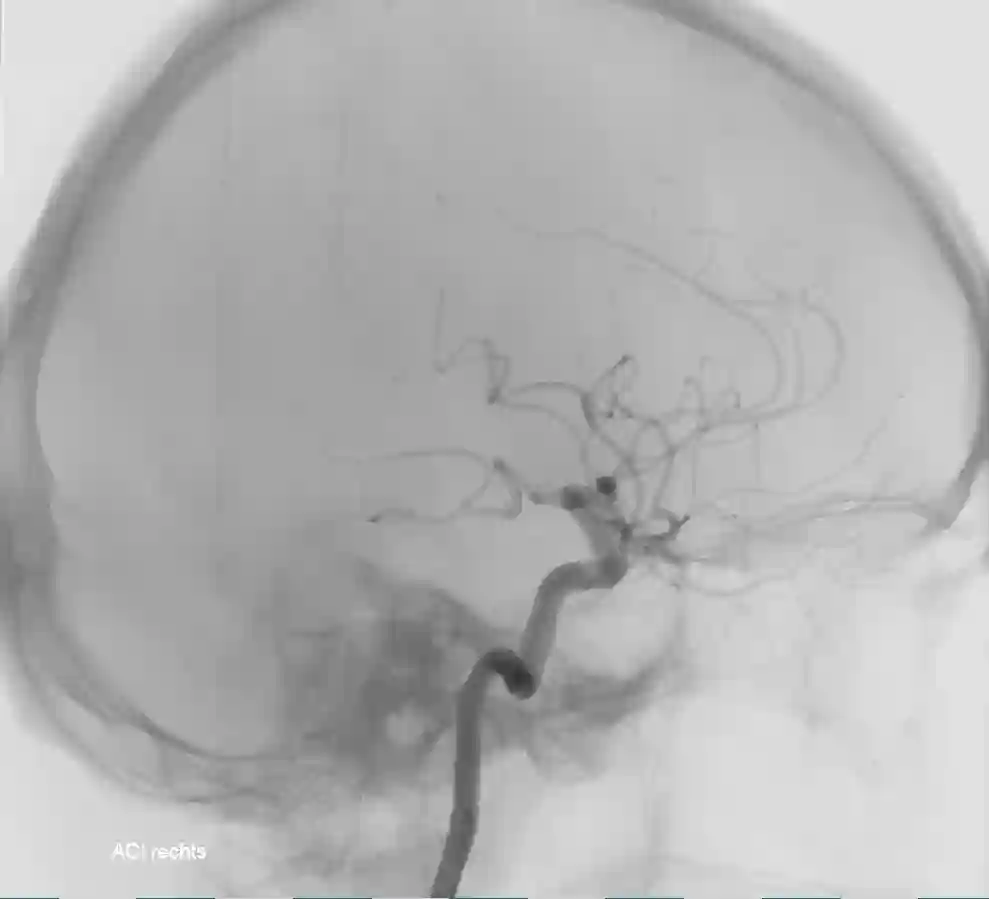

ICA Angiographie lateral

Darstellung der Arteria carotis interna in einer Angiographie im lateralen Strahlengang.